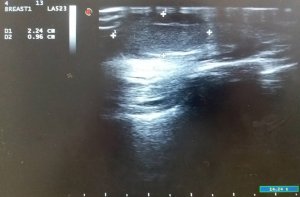

One year later, the patient discovered a swelling in the right nipple. Physical examination identified a non-mobile mass in the right nipple, measuring 2.0 cm in diameter (Figure 2), and no clear mass was found in the rest of the breast; other superficial lymph nodes were not significantly enlarged. Ultrasound examination revealed a regular hypoechoic masses (2.24 cm × 0.96 cm) in the right nipple (Figure 3). The mass in right nipple was resected under general anesthesia (Figure 4). The intraoperative pathological result accorded with PT. We confirmed the recurrence of PTs based on pathological findings. Then we continued to perform nipple-sparing mastectomy without immediate breast reconstruction, and also performed intraoperative frozen pathological examination of the margin of posterior nipple-areola complex. The pathological result of the incision margin was negative. Histopathological examination confirmed a borderline PT of the breast (Figure 5A). Immunohistochemistry of the tissue was positive for Vimentin, CD34, and Ki-67 (Figure 5B,C,D). The patient was discharged home and refused to receive adjuvant radiotherapy. Two years later, she remains disease free with no signs of recurrence (Figure 6).